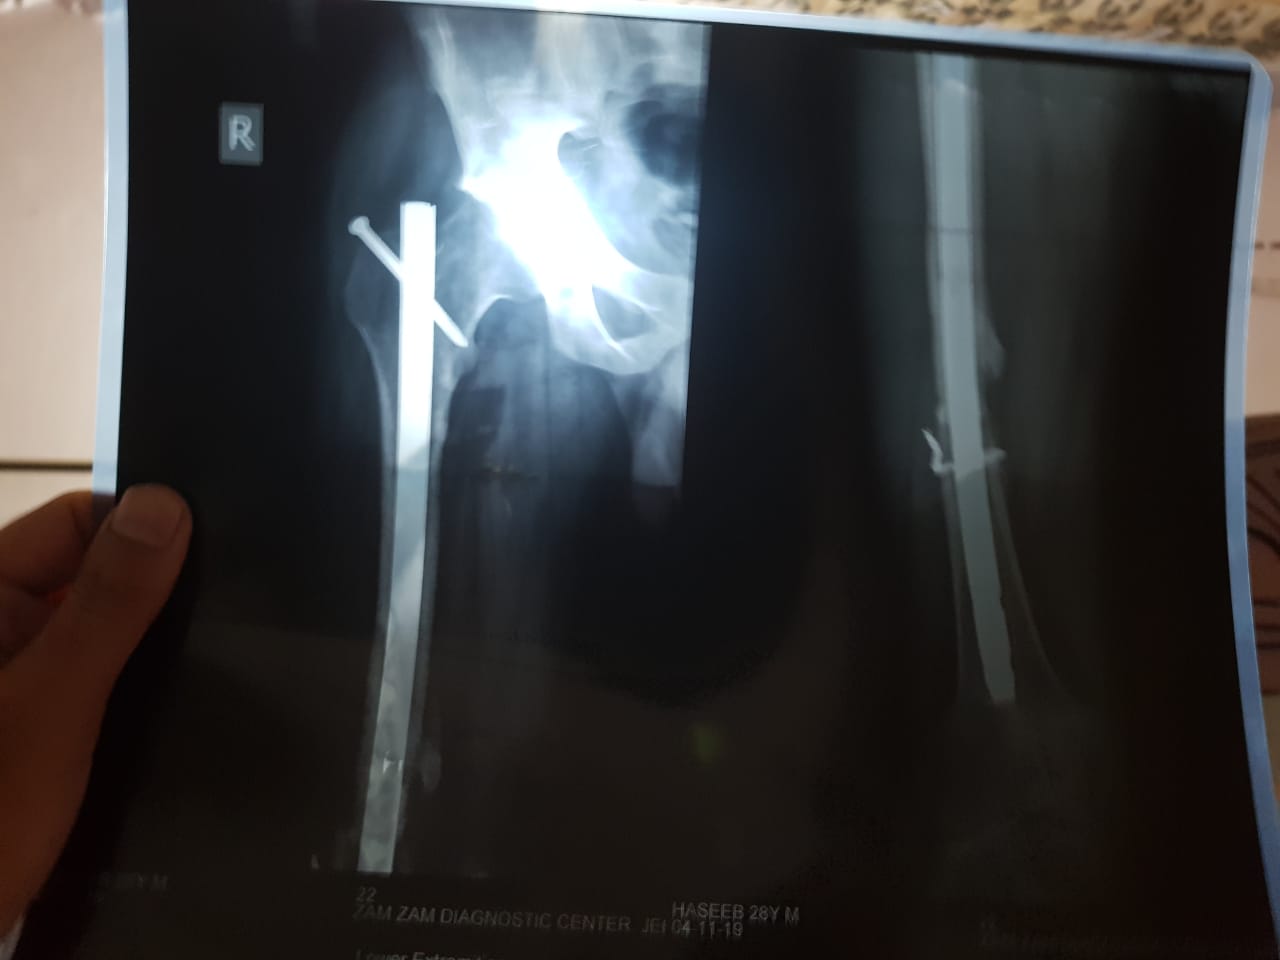

Meri age 29 ha 10 month phelay accident hua tha jis ma femur fracture hui or Rod dala lakin ma abi tak thek Tara say chal nai sakta Dr khetay ha dobara surgery karwou or bone grafting ho ge lakin ma chahta hu k mujay koi acha dr milay jo bether guide karay plz help me

Is it infected?. If not them start walking full wt bearing as alignment is good. It seems the surgeon did overreamed and applied big . and seems applied by open reduction so bone blood supply is compromised inside out by the operation. Best is walk on it and go to Nescom Hosp. Islamabad for Hyperbaric Oxygen therapy.